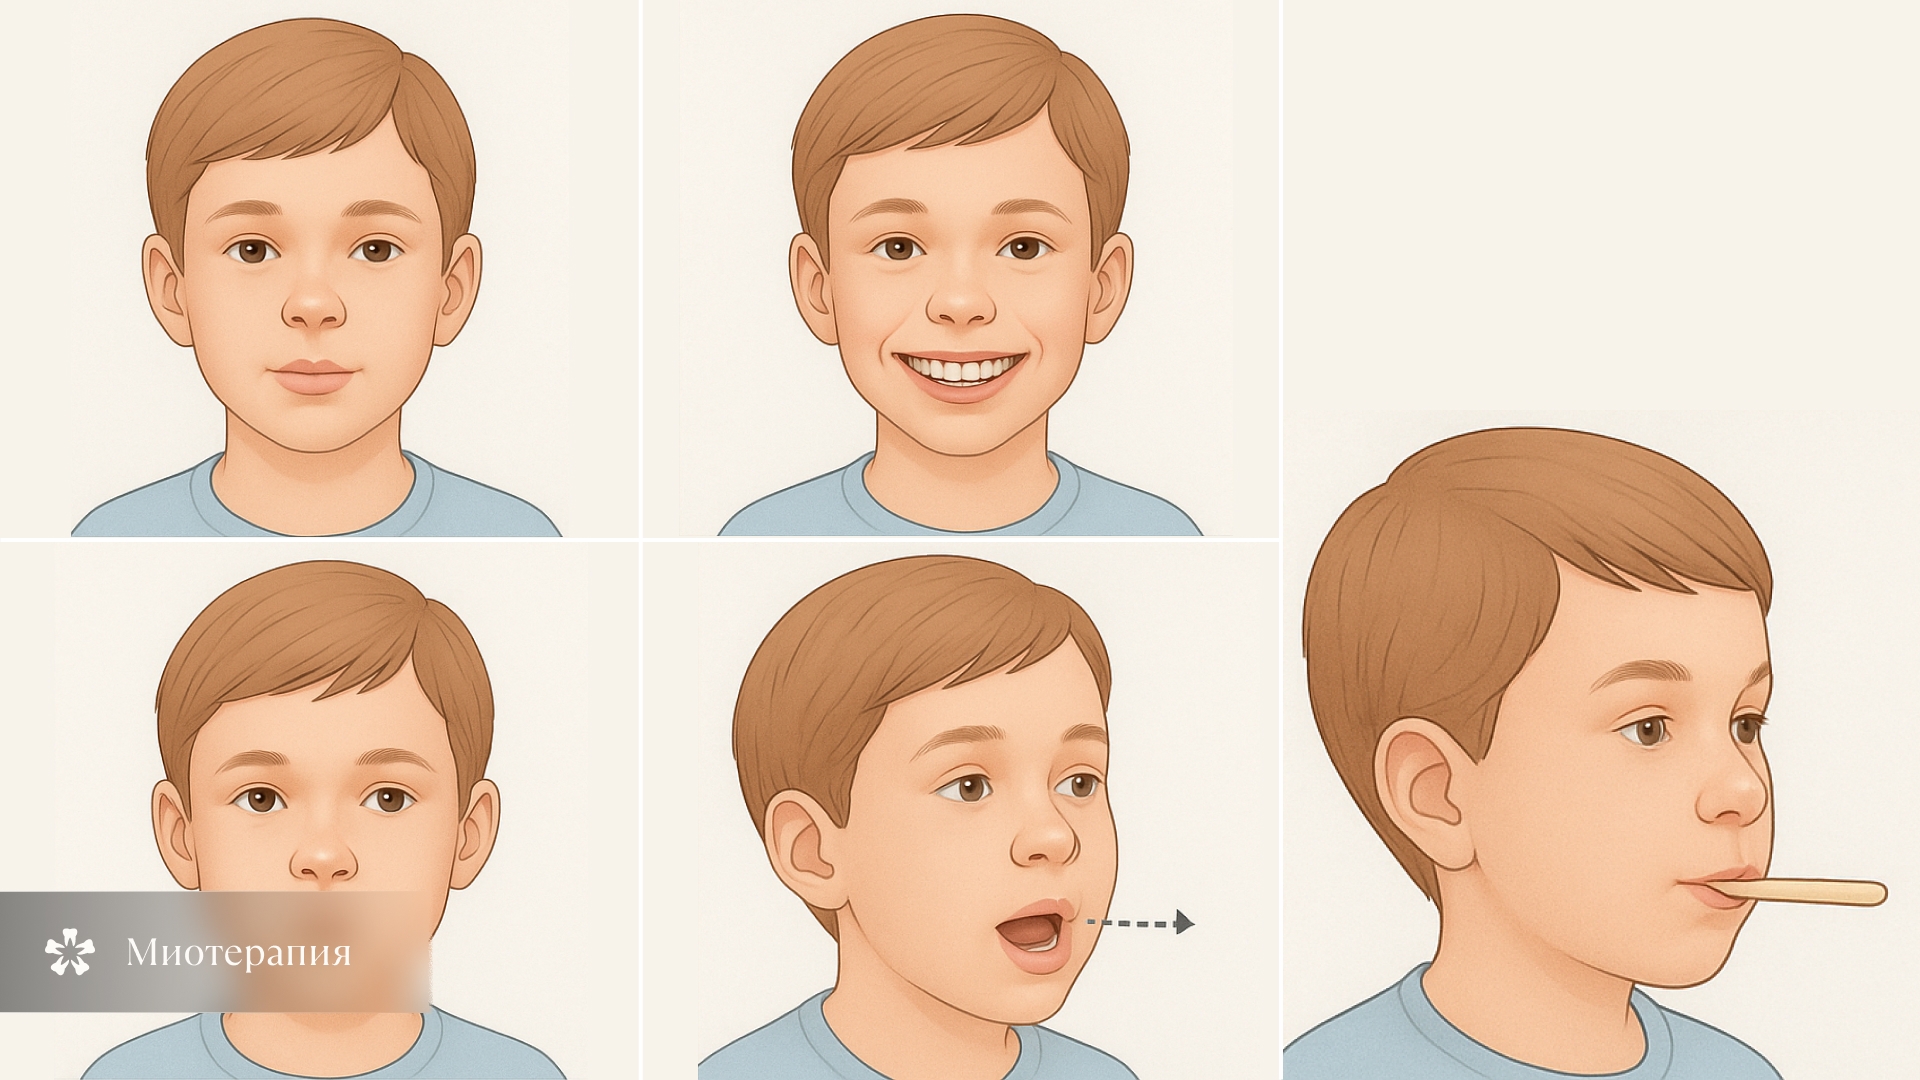

Миотерапия

Выполнение комплекса упражнений для укрепления лицевых мышц. Регулярные занятия миогимнастикой при дистальном прикусе у ребенка помогают костным структурам постепенно принять необходимое положение. Как правило, миотерапия используется в дополнение к иным методам ортодонтического лечения у детей старше 4 лет.

- Миогимнастика. Комплекс упражнений для укрепления лицевых мышц. Они стимулируют развитие нижней и одновременно замедляют рост верхней челюсти. При регулярном выполнении помогают постепенно придать костным структурам верное расположение.